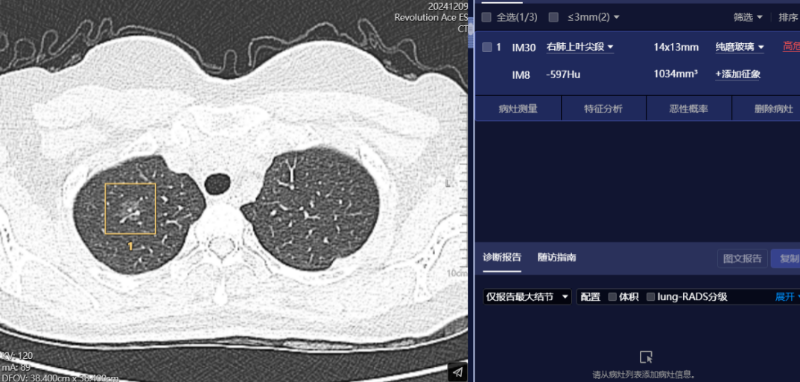

肺部結節(jié)篩查

肺癌是世界范圍內(nèi)患病率和病死率最高的惡性腫瘤之一。如果能在早期階段(尤其是Ⅰ期)進行手術切除,可顯著改善肺癌患者預后。然而,癌前病變、微浸潤性或浸潤性腫瘤常表現(xiàn)為磨玻璃結節(jié),密度淺淡,傳統(tǒng)的醫(yī)師肉眼診斷漏診率高。

AI人工智能憑借其準確的算法模型,能在短時間內(nèi)檢出,能對其進行定位定性、生長預測、預測惡性病變的病理分級及轉(zhuǎn)移和預后等。在堅持定期CT掃描的情況下,可以早期發(fā)現(xiàn)肺病變,提高治愈率。通常情況下,一位患者的常規(guī)胸部CT薄層圖像超過300幅,高年資影像診斷醫(yī)師肉眼觀察肺窗需超過5-10分鐘,而AI在幾秒內(nèi)即可對CT圖像進行自動識別、自動定位結節(jié)所在的影像層面與解剖位置,自動測量病灶結節(jié)大小、CT值等關鍵參數(shù),并自動對結節(jié)類型進行分型,自動預測結節(jié)病灶的惡性概率。